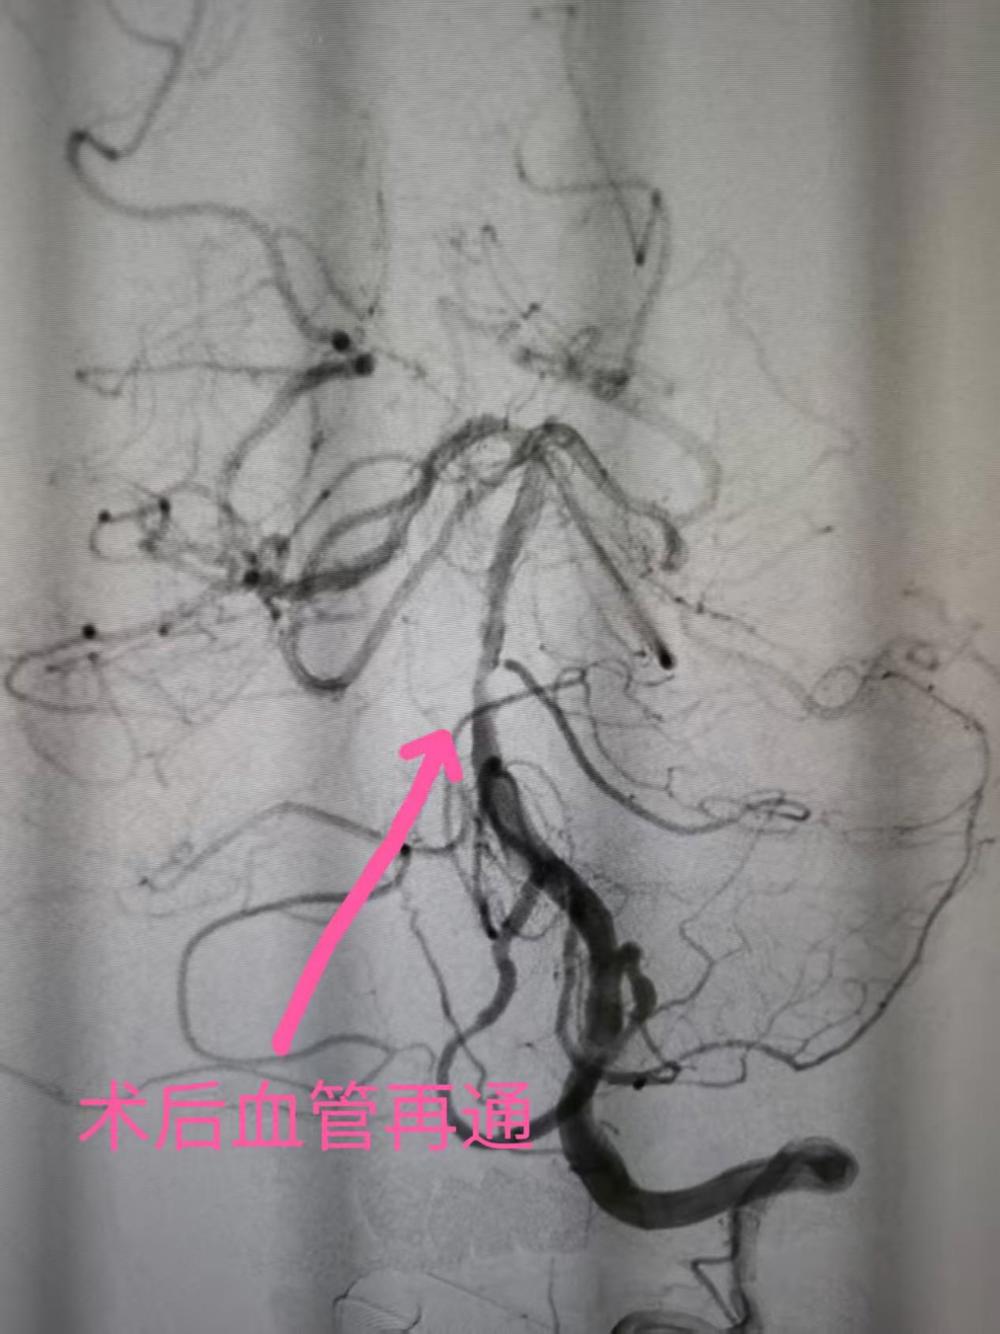

神经内科胡华林主任及其介入团队快速制定手术方案。通过介入取栓加脑血管球囊扩张成形手术,成功开通了闭塞的基底动脉,从穿刺到基底动脉首通时间为20分钟,黄先生的基底动脉成功恢复了血流再通。手术非常顺利,黄先生术后言语恢复清晰,能够自由下床活动,基本完全恢复正常。